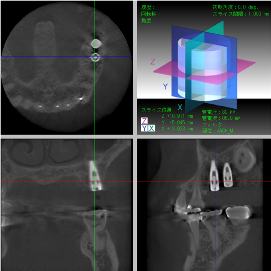

骨再生した箇所にインプラントを埋入します。

CTで治療計画を綿密に練ったうえで行いました。

インプラント埋入

インプラント埋入後のレントゲン画像です。